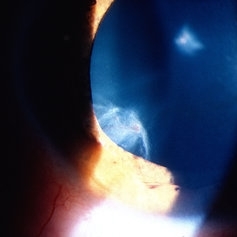

Siderosis

May 2 2013 by Henry J. Kaplan, MD

Iron deposition in the iris epithelium and sphincter and on lens epithelium in the same patient ; #2.

Condition/keywords: siderosis